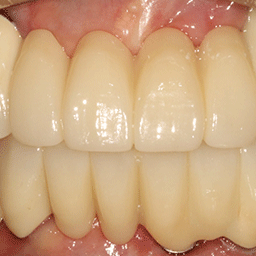

보철물 연결

보철물을 연결하여 자연치아와 같은 모습과 기능을 재현합니다.

W Dental Clinic Before & After

치료 전후사진

Before

After